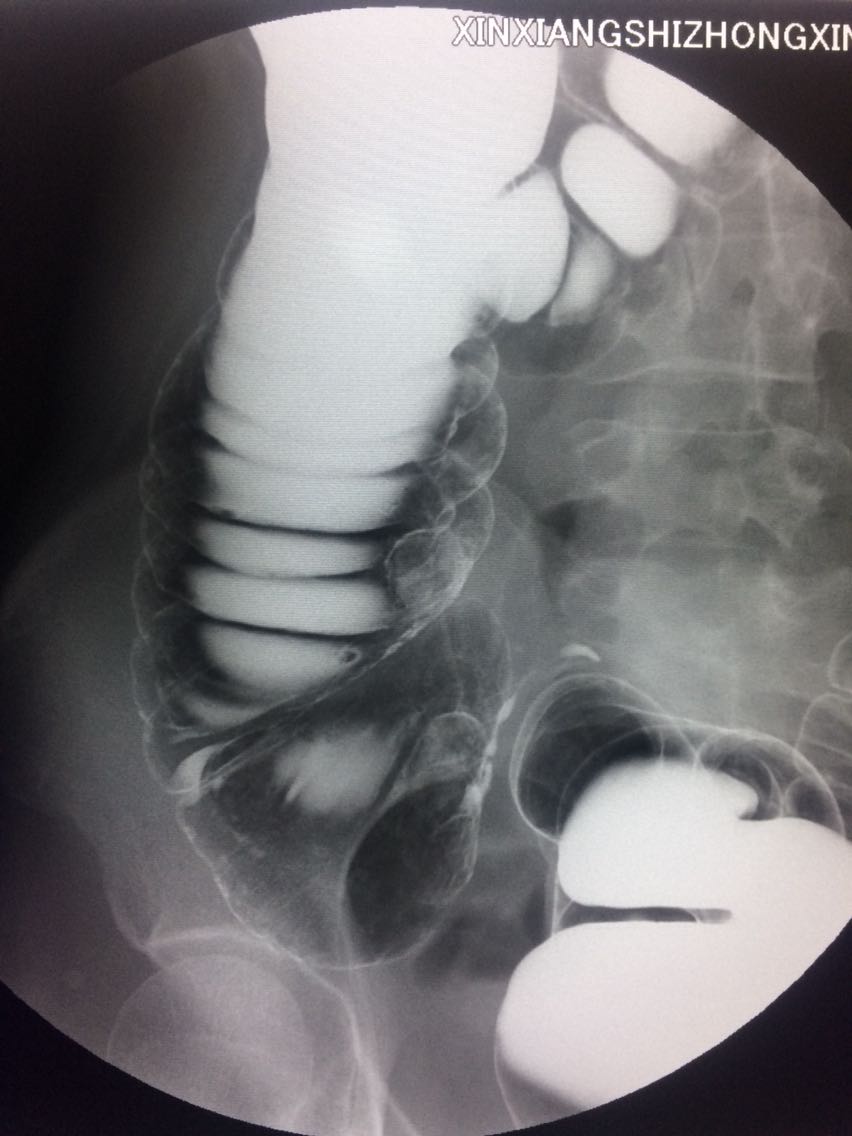

间断右下腹疼痛6年余。 6年来,无诱因出现右下腹痛,间断发生,呈胀痛,可忍受,压痛,无反跳痛。 既往:3年前,做肠镜未见明显异常。

查体,右下腹压痛。 入院做钡灌肠造影。

考虑升结肠占位。 完善术前各项检查。手术治疗。